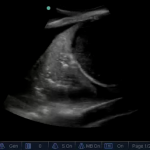

Diaphragm thickening of more than 30% suggests extubation will succeed according to this small but interesting study.